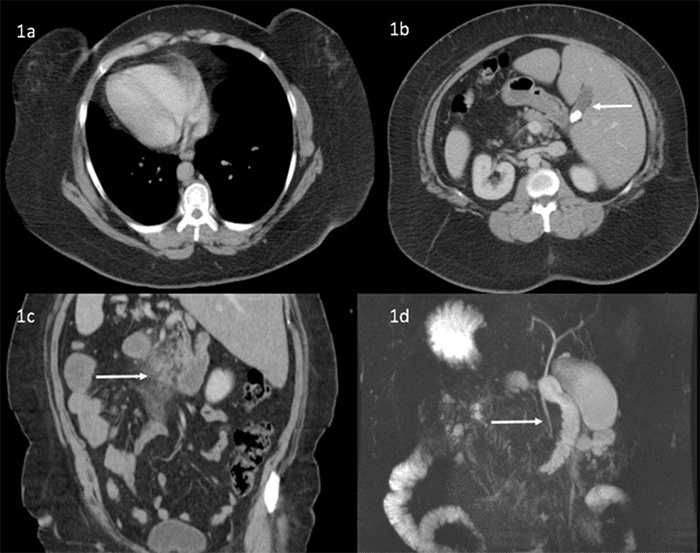

A 54-year-old white woman with SIT, hypertension, gastroesophageal reflux, and a history of transabdominal hysterectomy presented to the emergency department with seven days of left upper quadrant and epigastric pain after fatty meals. Physical examination revealed left upper quadrant tenderness and a lower midline laparotomy scar. Laboratory studies showed elevated lipase (404), leukocytosis (WBC 11), and normal liver function tests. Ultrasound confirmed cholelithiasis without acute cholecystitis and demonstrated SIT anatomy. CT of the chest, abdomen, and pelvis revealed SIT, pancreatitis, and duodenitis (Figure 1A-C). MRCP, obtained per gastroenterology recommendation, was negative for choledocholithiasis (Figure 1D), and an EGD was normal. A diagnosis of gallstone pancreatitis was made.

Figure 1. Preoperative Imaging Findings. Published with Permission

(A) Dextrocardia. (B) Liver and gallbladder (white arrow) located in the left upper quadrant. (C) Acute pancreatitis (white arrow). (D) Magnetic resonance cholangiopancreatography demonstrating no choledocholithiasis (white arrow)